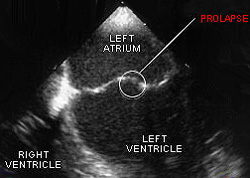

Сердце человека состоит из четырех камер – двух желудочков и двух предсердий. Во время сокращения предсердия митральный клапан (перегородка между левым предсердием и левым желудочком) пропускает кровь в желудочек. В норме после этого он плотно закрывается, но при пролапсе клапан прогибается, что является причиной обратного поступления небольшого количества крови в предсердие. В отдельных случаях величина оттока крови столь высока, что пациенту требуется хирургическая коррекция порока.

Пролапс митрального клапана – это провисание одной или обеих створок митрального клапана в полость левого предсердия во время систолы – сокращения желудочков сердца. Митральный клапан – образование, расположенное между левым предсердием и левым желудочком и состоящее из клапанного кольца, двух створок и поддерживающего створки подклапанного аппарата – хорд и сосочковых мышц. Во время систолы (сокращения) предсердий клапан открыт, и кровь свободно поступает в желудочек. Затем он закрывается, и во время систолы желудочков, когда кровь направляется в аорту, препятствует обратному току крови – регургитации - из желудочка в предсердие. В норме створки митрального клапана должны смыкаться полностью. Если этого не происходит, то некоторая часть крови забрасывается в левое предсердие.